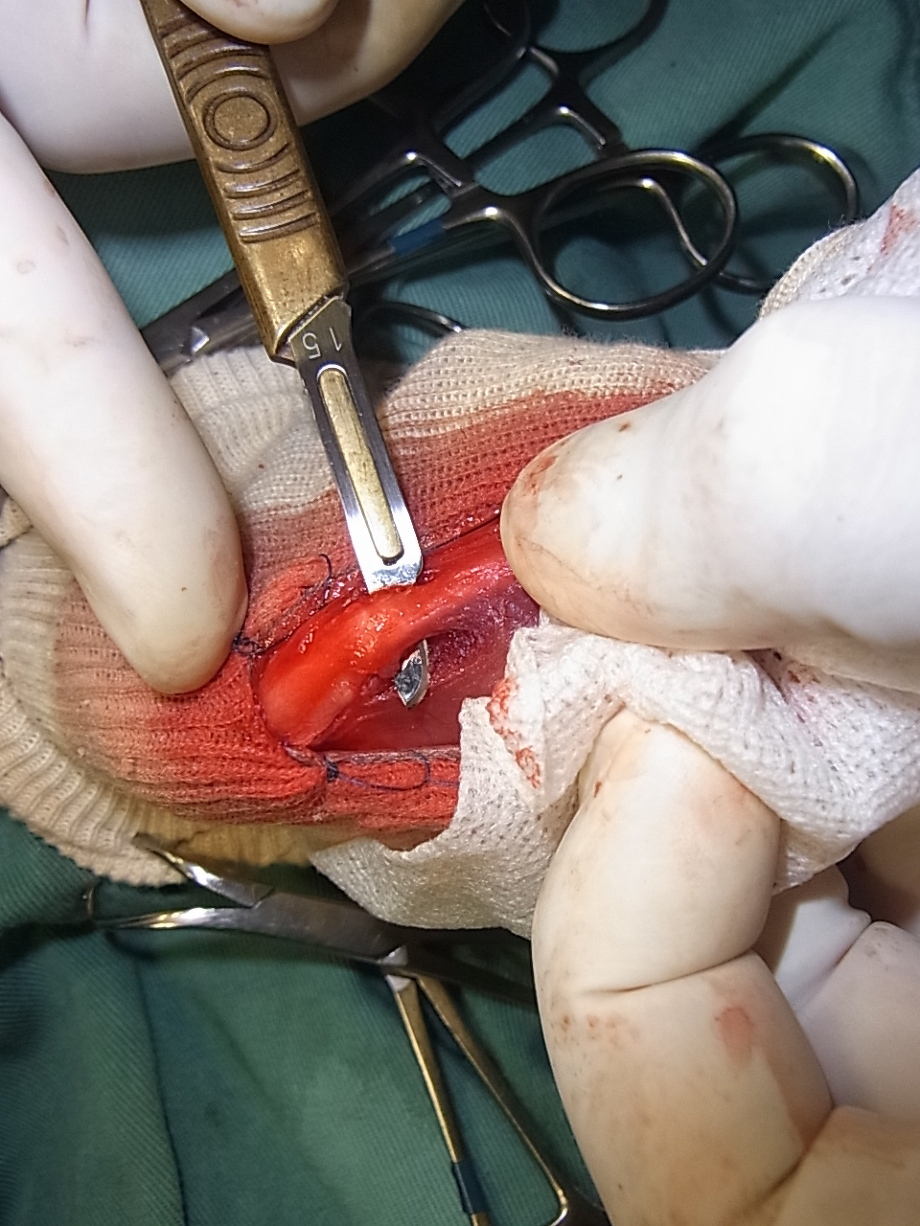

脛骨粗面をメスで切っています。